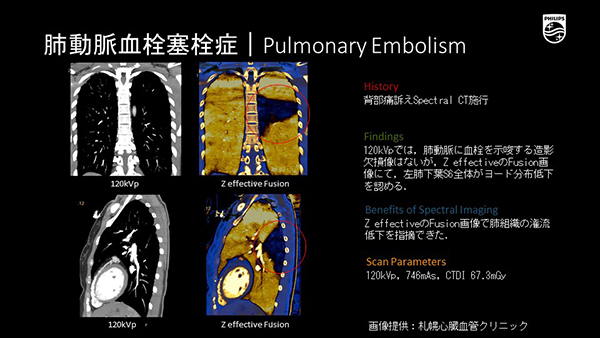

スペクトラルCT 基本原理と臨床応用』 | 学研出版サイト

スペクトラルCT 基本原理と臨床応用』 | 学研出版サイト,

スペクトラルCT 基本原理と臨床応用』 | 学研出版サイト, Dual Energy Imaging ~頭頸部領域での臨床応用~ - シーメンス・ジャパン株式会社 - inNavi Suite,

Dual Energy Imaging ~頭頸部領域での臨床応用~ - シーメンス・ジャパン株式会社 - inNavi Suite, IQon スペクトラル CT - 64列/128スライス/2層構造 - 株式会社フィリップス・ジャパン,

IQon スペクトラル CT - 64列/128スライス/2層構造 - 株式会社フィリップス・ジャパン, シーメンスヘルスケア株式会社】 CT装置 Dual Energy Imagingの原理と解析の基礎 -放射線技師向け情報サイト│ラジくる,

シーメンスヘルスケア株式会社】 CT装置 Dual Energy Imagingの原理と解析の基礎 -放射線技師向け情報サイト│ラジくる, SPECTRAL CT 新たな局面を迎えたラボ用X線マイクロCT | 東陽テクニカ | “はかる”技術で未来を創る | ナノイメージング,

SPECTRAL CT 新たな局面を迎えたラボ用X線マイクロCT | 東陽テクニカ | “はかる”技術で未来を創る | ナノイメージング,